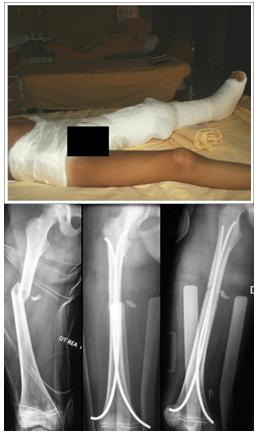

La sintesi viene realizzata con chiodi endomidollari in titanio secondo la tecnica di Nancy. In casi selezionati viene utilizzata la fissazione esterna (fissatore monoassiale o circolare). Torna su

Fratture di gamba

Anche per la tibia la capacità di autocorrezione della deformità assiale è molto spiccata. In particolare è marcata nelle deformità sullo stesso asse di movimento dell’articolazione, assai minore o nulla nelle deformità rotatorie.

Assai frequenti nell’età evolutiva sono le alterazioni dell’accrescimento quasi sempre rappresentate da un iperallungamento compreso fra 0,5 e 1,5 cm.

Il trattamento elettivo nelle fratture di tibia o biossee di gamba al di sotto degli 8-9 anni (raggruppando insieme metafisi prossimale, distale e diafisi) è conservativo. Nelle fratture con dislocazione dei capi ossei è necessaria l’applicazione di trazione tran-scheletrica calcaneare o tibiale distale a seconda del livello della lesione. Dopo periodo di trazione di 2-5 giorni la dislocazione viene ridotta con delicate manovre eseguite in narcosi e l’arto viene tutelato in apparecchio gessato inglobante il filo transcheletrico.

Per evitare scomposizioni secondarie il ginocchio andrebbe immobilizzazione oltre i 60° di flessione.

E’ tollerata una deviazione in varo-valgo di 5-10° e in procurvato-recurvato di 10°-15°.

E’ auspicabile un accavallamento dei capi di frattura di 0,5-1 cm. in modo da “assorbire” la quasi sicura ipercrescita post-traumatica.

Dopo 35 giorni la ginocchiera viene sostituita da apparecchio gessato deambulatorio/tutore.

Nei pazienti più grandi (>9-10 anni), in cui aumenta l’incidenza di traumi ad alta energia e fratture comminute, è necessaria una riduzione più precisa e maggiormente anatomica. Se questa non è possibile o se si rilevano perdite di riduzione nei controlli radiografici in gesso l’intervento di osteosintesi diventa indispensabile. In genere la tecnica utilizzata è la endomidollare a cielo chiuso con chiodi in titanio secondo la tecnica di Nancy.

Anche in questo caso preferiamo tutelare l’arto operato in gesso per 4 settimane sia a scopo antalgico sia per evitare eventuali perdite di riduzione parziali.